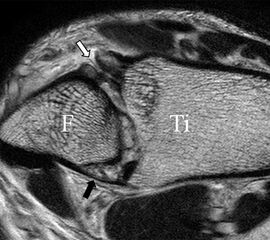

PD fs HR axial. Klare Darstellung eines filigranen, knapp über 1 mm breiten LFTA (Pfeil). Fibula (F).

Abbildung 3

Das LFTA verbindet die antero-inferiore Fibulaspitze mit dem Processus lateralis tali und inseriert hier an einem oder zwei kleinen Tuberkeln 3. Der in Neutralposition horizontale Verlauf erleichtert die kernspintomographische Darstellung in dieser Standardebene. Das LFTA weist durchschnittlich eine Breite von knapp über 2 mm auf 4. Somit sind bei einer Routinedarstellung in 3 mm Schichtdicke Anschnittsphänomene, die die Diagnostik erschweren, regelmäßig anzutreffen. Dementsprechend sind auch die ligamentären Subfaszikel nicht zu differenzieren. In koronarer Darstellung ist dies aufgrund der hohen Auflösung in der Schichtebene jedoch möglich (Abb. 2 a-c), wobei hier wiederum eine Integritätsbeurteilung des Bandes erschwert ist. Unter Verwendung hochauflösender Techniken im Millimeterbereich (Schichtdicke) sind hingegen auch in der axialen Ebene die subfaszikulären Strukturen zu beurteilen (Abb. 3).